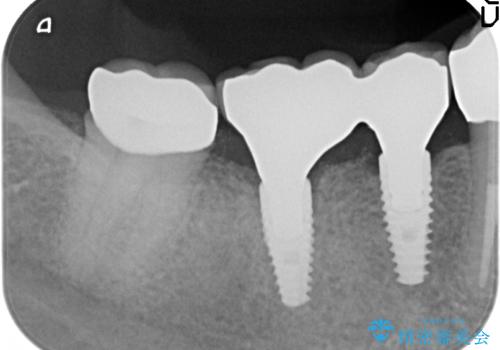

- 患者様は上顎の前歯のブリッジのところの圧迫感を主訴に来院されました。

右上の1番目から3番目にかけてブリッジを装着されており、歯茎も腫れて、ブラッシングもうまくできていない状況でした。

また高血圧症の既往があり、副作用として歯肉の腫れを引き起こすお薬を服用されていました。

治療計画は、まずブリッジを仮歯におきかえてからブラッシング指導と、歯周基本治療(歯石の除去とプラーク除去)をして改善が見られない場合は、違う種類の薬に変更可能かをを担当内科医に照会し、歯肉腫脹を改善後、最終的なブリッジを装着する計画となりました。

歯周治療後も歯肉腫脹が改善されないため、内科主治医へ薬の種類の変更が可能か問い合わせ、変更していただきました。その後、歯肉腫脹が改善したため金属の土台をファイバーコアに変更しオールセラミックにてブリッジを作成しました。